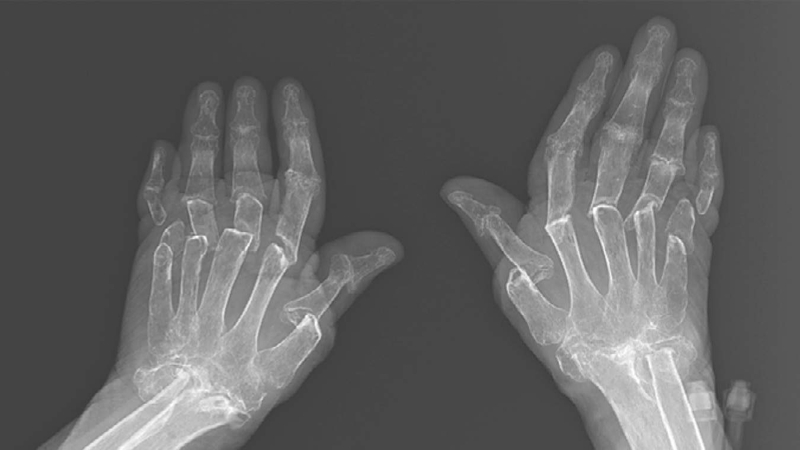

Quét hình ảnh xương khớp

Thông qua những hình ảnh này, bác sĩ sẽ thấy được rõ ràng từng ngóc ngách bên trong khớp cổ tay, bàn tay và cẳng tay Thông qua những hình ảnh này, bác sĩ sẽ thấy được rõ ràng từng ngóc ngách bên trong khớp cổ tay, bàn tay và cẳng tay

Hiện nay, ngoài chụp X-quang thì còn có nhiều công nghệ hiện đại khác để thu được hình ảnh xương khớp như CT scan hay MRI. Thông qua những hình ảnh, bác sĩ sẽ thấy được rõ ràng từng ngóc ngách bên trong khớp cổ tay, bàn tay và cẳng tay. Nhờ vậy có thể nhận diện chính xác tổn thương mà xương khớp đang gặp phải.